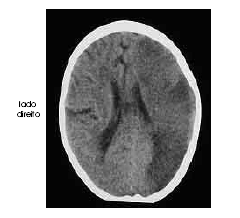

Um homem com 67 anos de idade, lavrador, deu entrada no pronto-socorro após ter sido encontrado, em sua casa, no chão e com dificuldade para falar e deambular. O paciente morava sozinho e os parentes não sabiam informar sobre uso de medicações ou patologias pregressas. Na avaliação, o neurologista identificou afasia mista, hemianopsia homônima direita e hemiparesia direita de predomínio braquifacial. Apesar de apresentar sonolência, o paciente ficava alerta ao chamado. A pressão arterial era de 180 mmHg × 90 mmHg. Foram solicitados exames complementares e de imagem, dos quais uma das imagens é reproduzida abaixo.

A partir da imagem retratada na figura acima, é correto inferir que se trata de acidente vascular cerebral com alteração de densidade à tomografia de extensa área de parênquima cerebral, razão por que deve ser contra-indicada a realização de trombolítico intra-venoso.